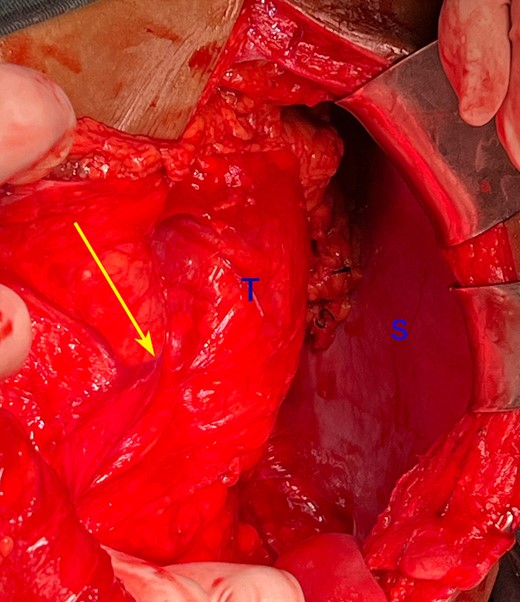

A man in his 30s presented with symptoms suggestive of irritable bowel symptoms with increased bowel movements coinciding with the onset of colicky abdominal pain for the past 8 months. The bowel movements relived his pain and had no remission from his symptoms. He had no relevant medical comorbidities in the past. The patient had normal vitals. There were no physical exam abnormalities except for a slight fullness in the left renal angle (Fig. 1). There was nothing significant on a rectal examination. An X-ray of the chest showed normal findings. Blood investigations showed: haemoglobin 130 g/l, total leukocyte: 7.4 × 109/l, serum creatinine 0.52 mg/dl, fasting blood sugar 90 g/dl, alanine transaminase 26 U/L, aspartate transaminase 42 U/L, alkaline phosphatase 32 U/L and total bilirubin 0.8 mg/dL. Ultrasonography showed a 10-cm mass, with mixed echogenicity. Posterior to the left kidney. Colonoscopy was normal. An abdominal CT scan showed a paravertebral tumour with peripheral enhancement and heterogenous contrast within the tumour (Fig. 2). The tumour showed high intensity on a T2-weighted MRI (Fig. 3). The left kidney and colon were displaced anteriorly. Fine-needle aspiration biopsy was inconclusive. The clinical diagnosis was a retroperitoneal schwannoma. On laparotomy, the left colic vessels appeared to be splayed by the tumour (Fig. 4). The tumour 11 × 6 × 3 cm3 (Fig. 5), which seems to be arising from the L2 nerve, was resected completely (Fig. 6). The patient had no sensory or motor loss postoperatively. He was discharged without complications on the 10th postoperative day. His colonic symptoms had disappeared after surgery. The gross appearance of the resected tumour showed cysts and haemorrhage patches (Fig. 7). Histopathology showed areas of hypercellularity (Antony A) and hypocellularity (Antony B) with degenerative changes leading to nuclear atypia and cystic spaces, typical of an ancient schwannoma (Figs 8–11). Immunohistochemistry with S-100 was positive (Fig. 12). He was devoid of digestive symptoms or radiological evidence of recurrence at 12 months.

Intraoperative photograph showing the left colic vessels are splayed (arrow) by the tumour (T). S: spleen.